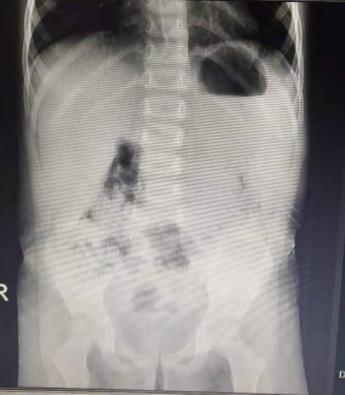

入院后赶紧帮孩子完善各项相关检查,查血常规、肝功能、肾功能、心肌酶、降钙素原、C反应蛋白、流感病毒抗原未见异常;鉴于孩子有肠套叠病史,赶紧再次查查胃肠彩超及腹平片看看,好在结果都是无问题的。